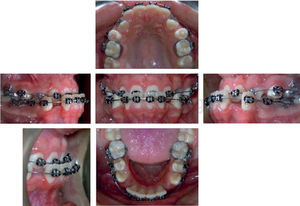

Culminada la nivelación, iniciamos el cierre de espacios inferior, se colocaron arcos 0.019 x 0.025” de acero inoxidable con hooks crimpables, block out posteriores (paredes para ocluir y favorecer el movimiento) y lace backs activos que se cambiaron mensualmente durante sus controles (Figura5).

La retracción del segmento anteroinferior fue complementada con el uso de elásticos intermaxilares con vector de clase III de 3/16 31/2 onzas, en ese momento se eliminaron los block out posteriores y se colocaron en anterior manteniendo la posición dista de la mandíbula; durante dos meses fue la mecánica empleada y en la cita sucesiva se observó una relación dental clase II asociada al uso de los elásticos intermaxilares, por lo que se indicó una tomografía de cóndilo con boca abierta y boca cerrada, cefálica lateral y panorámica para la valoración de la posición condilar (Figura 5).

Evaluada la tomografía axial y la panorámica; se encontró una posición condilar adecuada y se decidió la realización de mecánicas de pérdida de anclaje inferior y se indicó el uso de elásticos intermaxilares con vector clase II de uso nocturno, volviendo a obtener así la relación clase I canina perdida (Figura 6).

En la fase de terminado se emplearon elásticos intermaxilares de cierre up and down con vector clase I, retirando los brackets de forma definitiva al cabo de dos años y siete meses discontinuos de tratamiento, con oclusión clase I molar y canina y perfil recto.